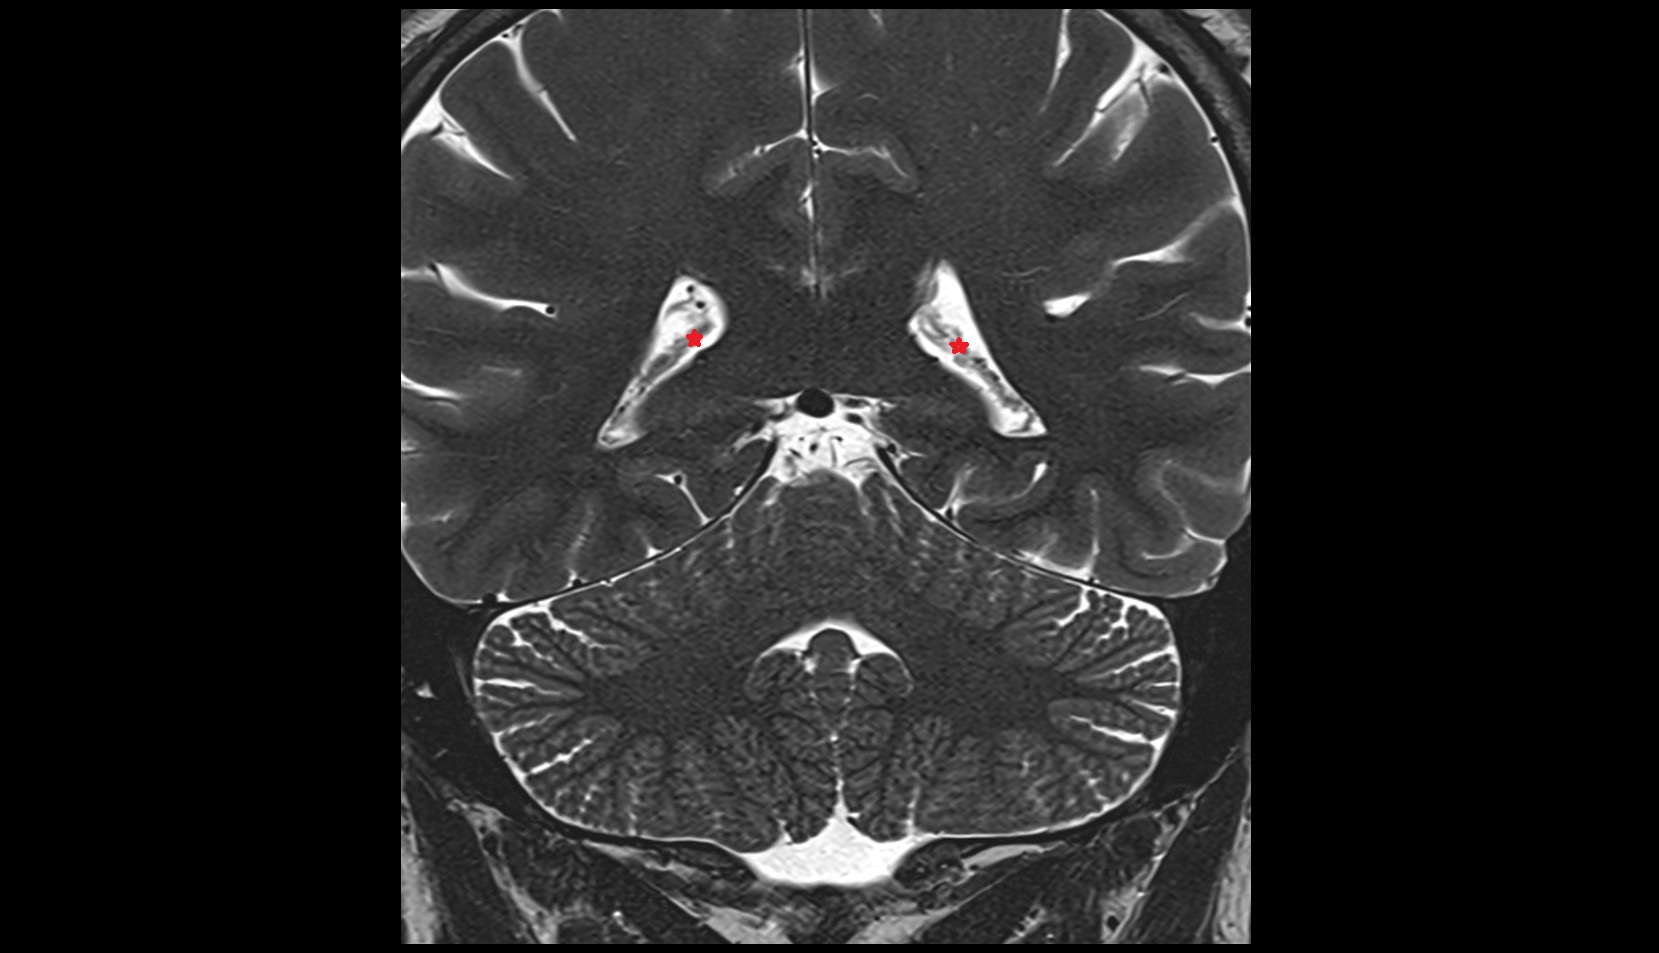

- Body of hippocampus

- Head of hippocampus

- Tail of hippocampus

- Hippocampus